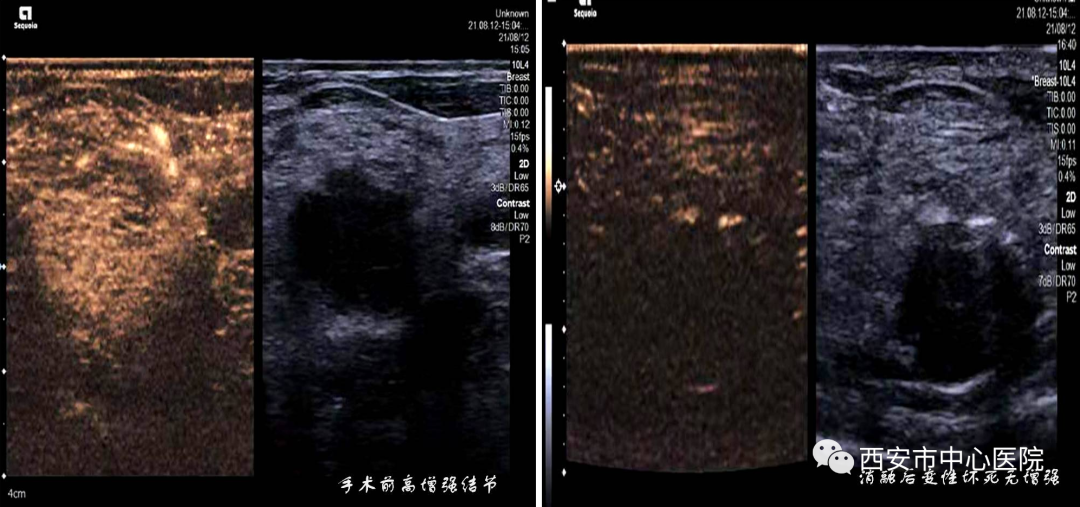

郑瑜主任团队高度重视此次治疗并做了充分的术前准备,乳腺多发结节的超声造影显示“均匀性增强,边界清晰”——果然是一个个高增强结节。郑瑜主任介绍说,这类良性高增强结节因为微血供比较丰富,容易不知不觉中慢慢长大,用射频消融进行精准的阻断血供并使瘤体变性坏死,对抑制良性结节生长是十分有效的方法。而且仅需要局麻辅助,痛苦小且术后无疤痕,做完即可回家,不影响工作生活,可多次进行。

仔细的观察和在超声的实时动态观察下,选择合适的穿刺路径,将射频针缓缓的插进乳腺结节内,能清楚的看见消融针的爆破和结节逐渐硬化过程,还可以根据患者自身状态,设定结节消融时间与功率,术后再次乳腺结节造影时发现乳腺结节消融区域无造影剂进入,与术前造影结果有明显对比,治疗效果立竿见影。